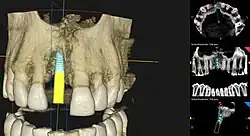

Planung

Die Planung einer Implantation geschieht je nach Komplexität der Situation mittels eines einfachen Zahnröntgens, oder durch Zuhilfenahme weiterer Hilfsmittel. Mit Hilfe einer Computertomographie (CT) oder einer Digitalen Volumentomographie (DVT) kann die Position des Implantats vor dem Eingriff festgelegt werden. Die Planung erfolgt dreidimensional am Computer und wird anhand einer individuell hergestellten Bohrschablone umgesetzt.[42] Nachteilig hierbei sind die Strahlenbelastung und die zusätzlichen Kosten für den Patienten.

Backward-Plannings

Beim Backward-Planning geht die Planung der Implantation nicht von der Kiefer- und Knochensituation aus, sondern vom Zahnersatz. Die Position der Implantate richtet sich sozusagen rückwärts nach der Stellung der neuen implantatgetragenen Zähne. Aufgrund von Abformungen und dreidimensionalen Bilddaten entwickelt das Zahnlabor ein Modell des späteren Zahnersatzes. Anhand dieses Modells ermittelt der Implantologe – mit computergestützter 3D-Implantatplanung – die geeignete Zahl, Position, Länge, Ausrichtung und Bohrtiefe für die Implantate. Auch hier wird die individuelle Knochen- und Weichteilsituation berücksichtigt.[42]

Per Bohrschablone wird für eine präzise Platzierung die digitale Simulation in den Mund übertragen.

Navigierte Implantologie

Die navigierte Implantologie ist ein prothetisch-chirurgisches Hilfsverfahren, um das richtige Setzen von Zahnimplantaten in den Kieferknochen zu erleichtern. Die Indikationen und Anwendungseinschränkungen für eine navigierte Implantation sind in den Guidelines der European Association of Osseointegration (EAO)[50] sowie für den deutschsprachigen Raum in der S2-K-Leitlinie der Deutschen Gesellschaft für Zahn-, Mund- und Kieferheilkunde (DGZMK) festgehalten.[51] Die meisten Indikationen beziehen sich auf eine Erweiterung der diagnostischen Möglichkeiten zur dreidimensionalen Darstellung der Kieferknochen und deren Nachbarstrukturen, um vor allem bei einem geringen Knochenangebot oder dessen unklarer Darstellung in den konventionellen Aufnahmetechniken eine verbesserte Einschätzung des OP-Gebietes zu ermöglichen.[42]

Bei einem minimalinvasiven Vorgehen wird das Implantatbett für das Miniimplantat präpariert, ohne einen Mukoperiostlappen zu bilden. Die vereinfachte und kürzere Operation kann eventuelle postoperative Beschwerden reduzieren. Orientierungshilfe bietet eine Bohrschablone.[42]